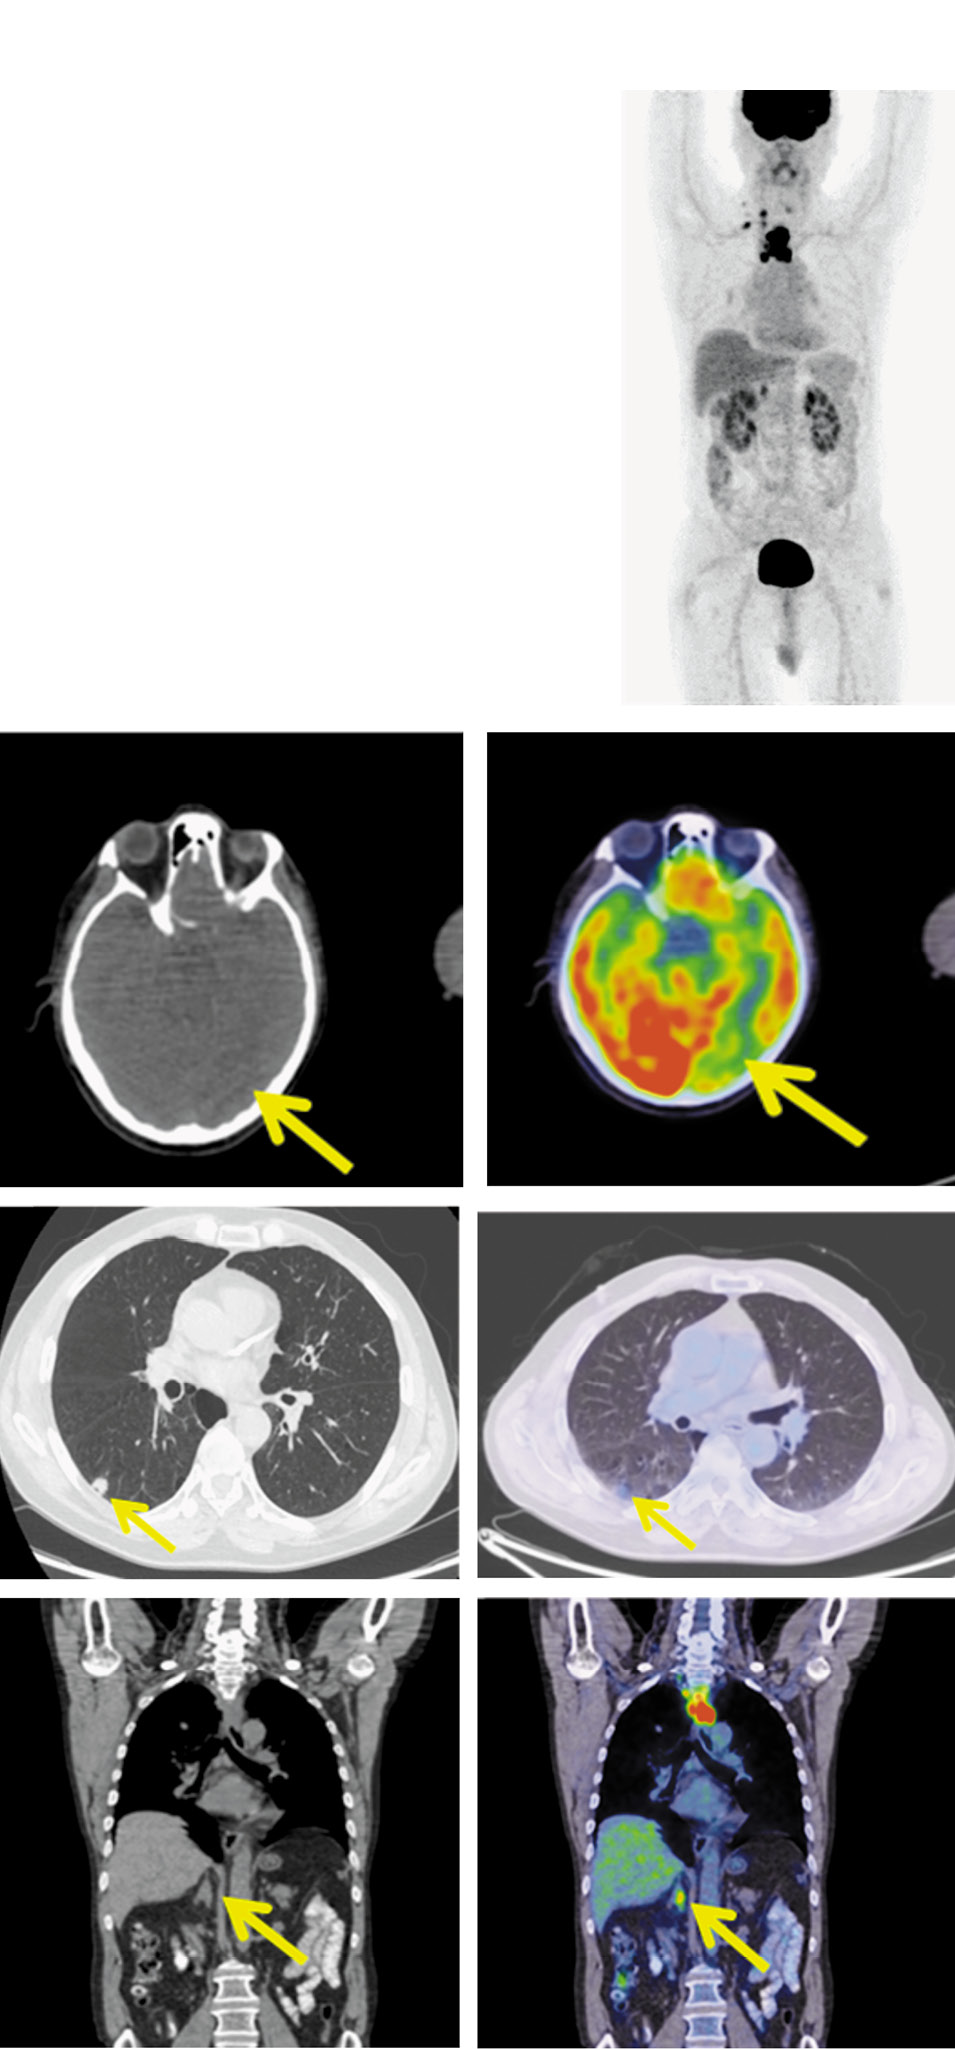

Рис. 3. Пациент Н.,64 года. После 3 циклов лечения. На MIP, аксиальной и корональной КТ и ПЭТ/КТ-проекциях в левой затылочной доле очагов фиксации РФП нет. Латеральный шейный лимфатический узел справа не определяется, а надключичный – 6 мм с фоновой фиксацией (SUVmax=2,35, ранее – 6,070). Субплеврально в S6 правого легкого – образование размером до 11×13 мм с метаболической активностью ФДГ (SUVmax=2,09). В средостении ретротрахеально справа сохраняется инфильтрат, сливающийся с правой стенкой пищевода, размером до 14×23×27 мм, ранее – 19×41×58 мм, с фоновой метаболической активностью ФДГ (SUVmax=3,12, ранее – 14,30). Лимфатические узлы: преваскулярные – размером до 5 мм, ранее – 9 мм без метаболической активности ФДГ; паратрахеальные верхней группы не дифференцируются. Регресс опухоли в правом надпочечнике.

Fig. 3. A 64-year-old patient N. The condition of the patient after 3 cycles of treatment. MIP, axial and coronal CT and PET/CT images show the left occipital lobe without increased uptake of radiopharmaceutical. The right lateral cervical lymph node is not detected, but there is a supraclavicular lymph node measuring 6 mm with background FDG uptake (SUVmax=2.35, previously – 6.070). In the subpleural section of the right lung S6 segment there is a lesion measuring 11×13 mm with FDG uptake (SUVmax=2.09). The infiltrate, merging with the right esophageal wall, measuring 14×23×27 mm, previously – 19×41×58 mm, with background FDG uptake (SUVmax=3.12, previously – 14.30) is still detected in the mediastinum in the right retrotracheal space. The lymph nodes: the prevascular lymph nodes measuring 5 mm, previously – 9 mm without FDG uptake; the upper paratracheal lymph nodes group is not differentiated. The regression of the tumor on the right adrenal gland.

В связи с появлением очаговой симптоматики проведено тотальное облучение головного мозга, разовая очаговая доза (РОД) 5 Гр, суммарная очаговая доза (СОД) 20 Гр, с применением радиомодификатора – темодала. После этого выполнена биопсия надключичного лимфатического узла. При гистологическом и иммуногистохимическом исследовании обнаружены метастазы плоскоклеточного рака. При иммуногистохимическом исследовании уровень экспрессии PD-L1 составил 90%. Активирующих мутаций в генах EGFR, ALK и ROS1 не выявлено. Учитывая распространенность опухолевого процесса, с 08.04.2019 больному начата иммунотерапия ингибитором PD-L1 атезолизумабом в дозе 1200 мг с интервалом 21 день. Проведено 3 цикла. Нежелательных явлений не отмечалось. С целью оценки эффекта проводимой терапии 25.06.2019 (после 3 циклов терапии) выполнена ПЭТ/КТ с 18-ФДГ. В левой затылочной доле очаги фиксации радиофармпрепарата (РФП) не дифференцируется. Латеральный шейный лимфатический узел справа не определяется, надключичный – до 6 мм с фоновой фиксацией, SUVmax=2,35 (ранее – 6,07). Субплеврально в S6 правого легкого – образование размером до 11×13 мм, с метаболичес- кой активностью ФДГ (SUVmax=2,09). В средостении ретротрахеально справа сохраняется инфильтрат, сливающийся с правой стенкой пищевода, размером до 14×23×27 мм, ранее – 19×41×58 мм, с фоновой метаболической активнос- тью ФДГ (SUVmax=3,12, ранее – 14,30).

Лимфатические узлы: преваскулярные – размером до 5 мм (ранее – 9 мм без метаболической активности ФДГ); паратрахеальные верхней группы не дифференцируются. Образование в правом надпочечнике регрессировало. По критериям RECIST v.1.1 получена частичная клинико-метаболическая регрессия (рис. 3).